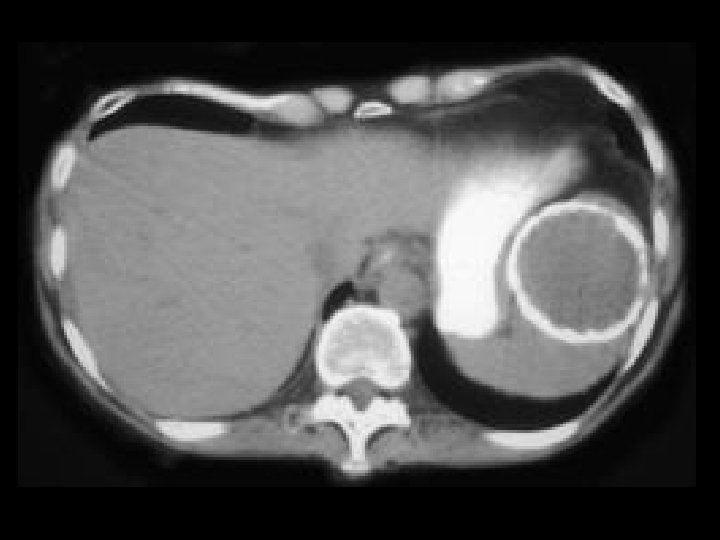

Von-Hippel Lindau • Findings: – Numerous bilateral renal cyst – Solid enhancing right renal mass = RCC • ddx: – NONE! – This is an Aunt Minnie!